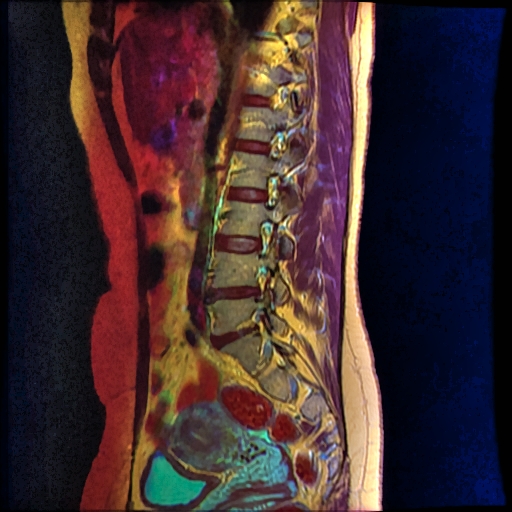

Color MRI of the Lumbar spine with extruded disc

Color MRI of the Lumbar vertebrae with extruded disc bit.ly/Color_MRI

- T1W FSE in red channel

- T2W frFSE in green channel

- STIR in blue channel.

- Yellow: Orange

- Water: Green-Blue

- Muscles: Purple